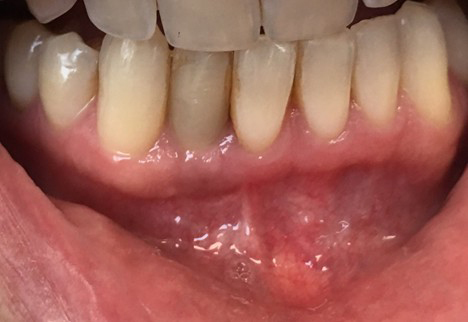

Patient Presentation:

A 47-year-old healthy female patient presented to the clinic with complaints of discomfort and occasional swelling around a dental implant in the region of tooth #42 (lower right lateral incisor). The implant had been placed approximately one year prior to her complaint. The restoration of the implant was performed by an external provider. Initial osseointegration and function had been reported as successful. The implant was clinically, radiographically, and ISQ tested prior to sending her back to the referring dental clinic for restorative care. Over the past several months, post-implant restoration, the patient had noticed bleeding while brushing the implant, mild purulent discharge, and gingival pain and swelling.

Clinical & Radiographic Examination Sequence

Findings:

Clinical examination revealed inflamed peri-implant soft tissue, probing depths of 6–8 mm circumferentially, and mild suppuration. No mobility was noted, but the buccal tissue appeared slightly recessed with grey shadowing of the gingival marginal tissues. A periapical radiograph was obtained and showed significant vertical bone loss around the implant extending apically, with crater-like defects on all aspects.